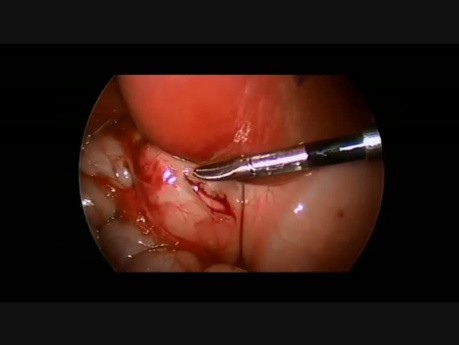

Apendicectomía laparoscópica

La apendicectomía laparoscópica es un enfoque muy efectivo en el manejo de la apendicitis aguda. Debido a su mayor latitud diagnóstica, menos dolor y recuperación temprana son sus principales beneficios.